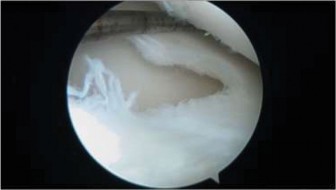

The correct answer is (C). The arthroscopic images demonstrate a complete discoid meniscus which is covering the entire lateral tibial plateau. As the patient is symptomatic from the meniscus, saucerization is the first step in management. The meniscus is trimmed back using a combination of shavers and biters to a stable peripheral rim, which replicates the width of the native meniscus. Complete meniscectomy would not be indicated in a patient of this age due to the high risk of early onset degenerative arthritis. In fact, even prior to intervention, many discoid menisci have been associated with the development of lateral hemijoint osteochondral lesions. Although chondroplasty may be necessary, the meniscus is the underlying problem causing chondral wear and must be dealt with first. After saucerization is performed, the meniscus is probed and the following arthroscopic image is seen (Fig. 10–33). The next step in management is:

Figure 10–33

4. Repair of the unstable peripheral rim of the meniscus

Discussion

The correct answer is (D). The arthroscopic image demonstrates an unstable peripheral rim of the meniscus which an attempt should be made to repair. The meniscus has been trimmed adequately but instability remains. Further saucerization without repair may lead to very little to no meniscus remaining which can lead to early degeneration. Although chondral damage may be present in association with the meniscus, there is no exposed subchondral bone to suggest the need for microfracture. Various repair techniques (inside-out, outside-in, all-inside) are available to the surgeon and should be utilized based on surgeon preference and experience. Objectives: Did you learn...?